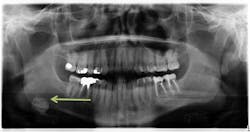

A healthy, 36-year-old male presented for a comprehensive exam. A panoramic radiograph revealed a well-defined, radiopaque lesion approximately 2x2 cm in size in the right submandibular region. The patient was unaware of its existence. The lesion was slightly palpable upon extraoral manipulation, but not necessarily tender.

Sialolith of the right submandibular gland

This particular patient was seen by an oral surgeon and a CT scan was obtained. It was recommended that the lesion be removed; however, since the lesion was asymptomatic at the time, the patient was quite reluctant. The patient is seen on a regular basis with subsequent radiograph evaluation to monitor for changes. The recommendation for removal still stands.